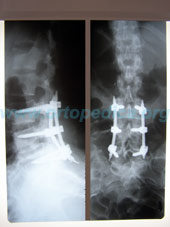

Рентгенограммы поясничного отдела позвоночника после хирургического лечения - транспедикулярной фиксации